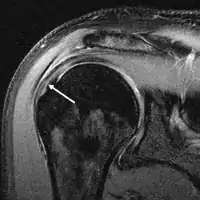

Diagnostic modalities, dependent on circumstances, include X-ray, MRI, MR arthrography, double-contrast arthrography, and ultrasound. Although MR arthrography is currently considered the gold standard, ultrasound may be most cost-effective.[34] Usually, a tear will be undetected by X-ray, although bone spurs, which can impinge upon the rotator cuff tendons, may be visible.[35] Such spurs suggest chronic severe rotator cuff disease. Double-contrast arthrography involves injecting contrast dye into the shoulder joint to detect leakage out of the injured rotator cuff,[36] and its value is influenced by the experience of the operator. The most common diagnostic tool is magnetic resonance imaging (MRI), which can sometimes indicate the size of the tear, as well as its location within the tendon. Furthermore, MRI enables the detection or exclusion of complete rotator cuff tears with reasonable accuracy and is also suitable for diagnosing other pathologies of the shoulder joint.[37]

MRI

Magnetic resonance imaging (MRI) and ultrasound[46] are comparable in efficacy and helpful in diagnosis, although both have a false positive rate of 15–20%.[47] MRI can reliably detect most full-thickness tears, although very small pinpoint tears may be missed. In such situations, an MRI combined with an injection of contrast material, an MR-arthrogram, may help to confirm the diagnosis. It should be realized that a normal MRI cannot fully rule out a small tear (a false negative) while partial-thickness tears are not as reliably detected.[48] While MRI is sensitive in identifying tendon degeneration (tendinopathy), it may not reliably distinguish between a degenerative tendon and a partially torn tendon. Again, magnetic resonance arthrography can improve the differentiation.[48] An overall sensitivity of 91% (9% false negative rate) has been reported, indicating that magnetic resonance arthrography is reliable in the detection of partial-thickness rotator cuff tears.[48] However, its routine use is not advised, since it involves entering the joint with a needle, with the potential risk of infection. Consequently, the test is reserved for cases in which the diagnosis remains unclear.